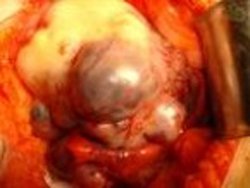

No hay que hacer cirugía, y solo en algunos casos cuando se practique laparoscopia, se pueden drenar estos “quistes” aplicando una técnica de RADIOFRECUENCIA, que es parecida al LÁSER.

Mira estas fotos: